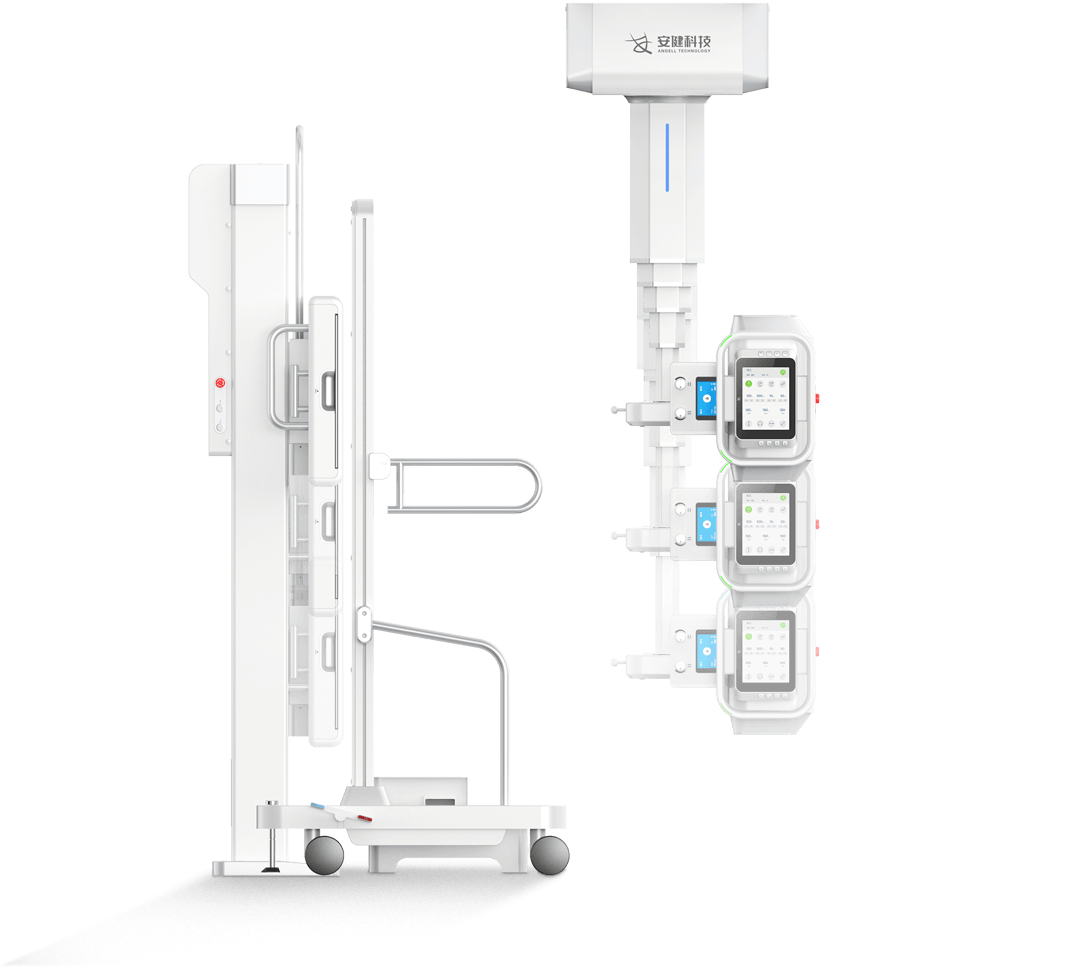

4D十轴联动运动系统

多功能悬吊式机械运动,全平衡稳定性设计,4D十轴联动技术,机架运动自如平稳,

配合电动升降床及多功能立式摄影架,轻松满足临床全体位摄影需求。

立卧位一键切换、—键到位

全自动智能运动控制,射频信号双向接收设计,

实现立卧位一键切换、一键到位,简化操作,提升效率。 -

电动升降床

超大行程运动范围,灵活应对儿童、老人、外伤患者上下床。

配备嵌入式感应解锁系统,轻松调节床高并有效避免患者误触。

动静双板自由切换

动态平板+静态平板双板配置,可实现毫秒级选板切换。

配合手自一体悬吊式机械运动系统,多体位拍摄转换轻松自如,大幅提升临床检查效率 -

低体位灵活拍摄

探测器和球管可降至紧贴地面,完成下肢多角度摄影,

减少病人移动,同时便于儿童立位、四肢拍片。 -

无线遥控操作

配备无线遥控器,遥控灵敏,设备运动反应迅捷,

全程支持隔室遥控操作。 -